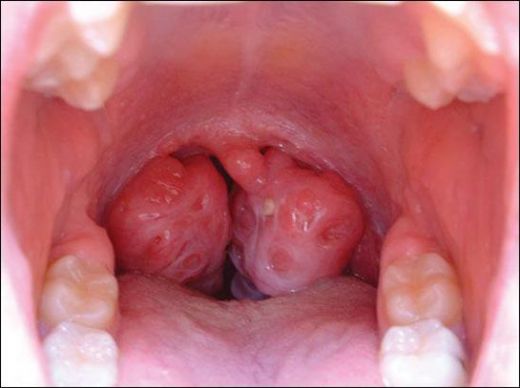

Kronik bademcik iltihabı, genellikle tekrarlayan bademcik enfeksiyonları sonucunda ortaya çıkan ve bademciklerin sürekli iltihaplanmasıyla karakterize edilen bir durumdur. Bu durum, bireylerin yaşam kalitesini olumsuz etkileyebilir. Aşağıda, kronik bademciğin belirtileri, nedenleri ve tedavi yöntemleri detaylı bir şekilde ele alınacaktır. 1. Kronik Bademcik Belirtileri Kronik bademcik iltihabı yaşayan kişilerde gözlemlenen belirtiler şunlardır:

Kronik bademcik iltihabının belirtilerini yaşayan biri olarak, sık sık boğaz ağrısı ve kötü nefes kokusu yaşıyorum. Büyümüş ve deforme olmuş bademciklerim de var. Bu belirtilerle sık sık karşılaşan biri olarak, boğaz enfeksiyonlarımın kronik bademcik iltihabından kaynaklanıyor olabileceğini düşünüyorum. Tedavi için hangi adımları atmam gerek?